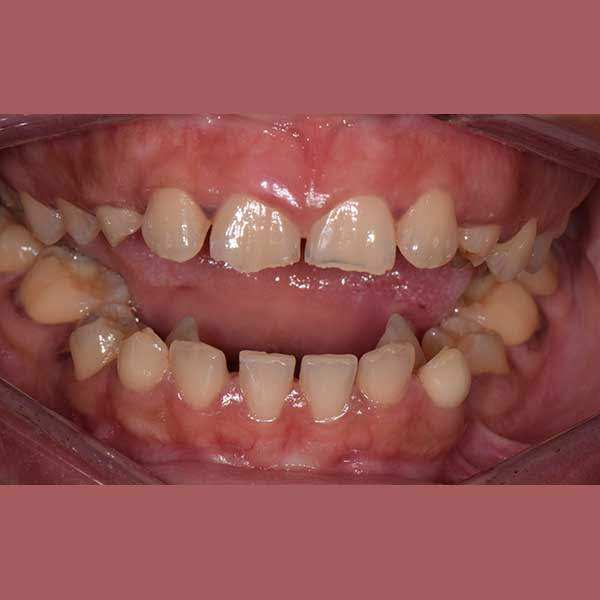

راجعتني هذه السيدة وهي تعاني من مشاكل معقدة؛ فأنيابها العلوية الدائمة لم تبزغ أبداً، وبقيت الأنياب اللبنية في مكانها. بالإضافة إلى ذلك، كانت أنيابها السفلية بازغة للداخل، مما سبب لها صعوبات كبيرة في الأكل والنطق وأفقدها الثقة بابتسامتها لدرجة أنها رفضت تصويرها في البداية.

بعد الفحص وأخذ الصور الشعاعية، أوضح الدكتور خالد الكاتب أن الأنياب العلوية موجودة ولكنها منطمرة بالكامل في عظم الفك، بالإضافة لوجود ضاحك سفلي منطمر أيضاً. وبسبب كبر سن المريضة، كان لا بد من خطة علاج متكاملة: